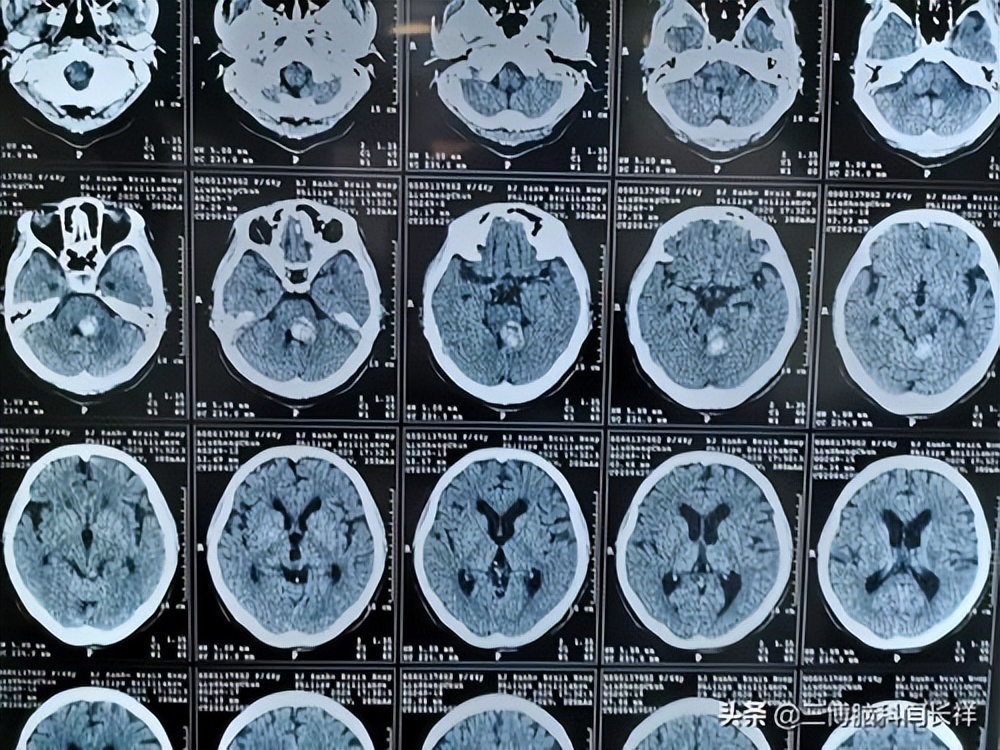

过了半个月左右,小刘的症状越来越严重了,在家人的督促下小刘来到了附近的三甲医院神经内科做检查,医生了解症状后 怀疑小刘的大脑除了问题,于是先给他开了CT检查,一个小时后检查结果出来了。

医生被吓了一跳, 在小刘的大脑脑干附近,有一个直径9cm的肿瘤病灶,与周围组织边界清晰,考虑脑血管瘤。

医生们赶紧将小刘送进了抢救室,先拍了CT, 发现小刘的脑血管瘤已经破裂出血,超高的颅内压将脑干压到了一边。